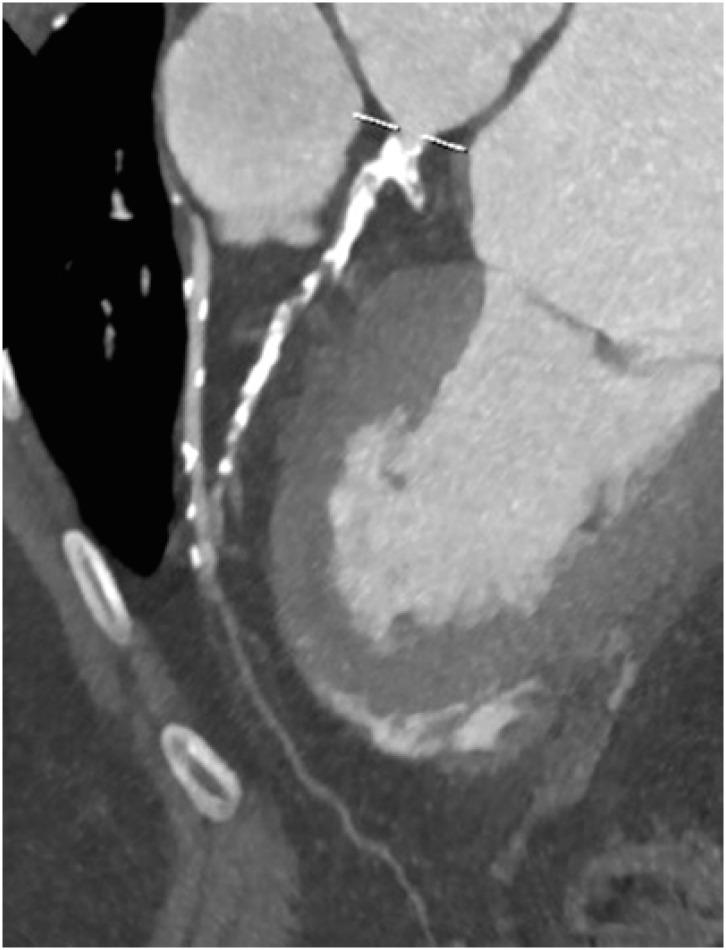

冠状动脉疾病报告与数据系统:全面综述。

Coronary Artery Disease Reporting and Data System: A Comprehensive Review.

The Coronary Artery Disease Reporting and Data System (CAD-RADS) is a standardized reporting method for coronary computed tomography angiography (CCTA). It summarizes the findings of CCTA in 6 categories ranging from CAD-RADS 0 (complete absence of coronary artery disease) to CAD-RADS 5 (total occlusion of at least one vessel). It is applied on per patient basis for the highest grade of the stenotic lesion. The CAD-RADS also provides category-specific treatment recommendations, helping patient management. The main objectives of the CAD-RADS are to improve the consistency in reporting, facilitate the communication between interpreting and referring clinicians, recommend the best course of patient management, and produce consistent data for quality improvement, research and education. However, CAD-RADS has many limitations, resulting into the misclassification of the observed findings, misinterpretation of the final category, and misguidance for the treatment based upon the single score. In this review, the authors discuss the CAD-RADS categories and modifiers, along with the strengths and limitations of this new classification system.

冠状动脉疾病报告与数据系统(CAD-RADS)是一种用于冠状动脉计算机断层扫描血管造影(CCTA)的标准化报告方法。它将CCTA的结果总结为6类,范围从CAD-RADS 0(完全不存在冠状动脉疾病)到CAD-RADS 5(至少一根血管完全闭塞)。它针对每位患者应用于狭窄病变的最高等级。CAD-RADS还提供特定类别的治疗建议,有助于患者管理。CAD-RADS的主要目标是提高报告的一致性,促进解读医生与转诊医生之间的沟通,推荐最佳的患者管理方案,并产生用于质量改进、研究和教育的一致数据。然而,CAD-RADS有许多局限性,导致观察结果的错误分类、最终类别的错误解读以及基于单一分数的治疗误导。在本综述中,作者讨论了CAD-RADS类别和修饰符,以及这个新分类系统的优点和局限性。